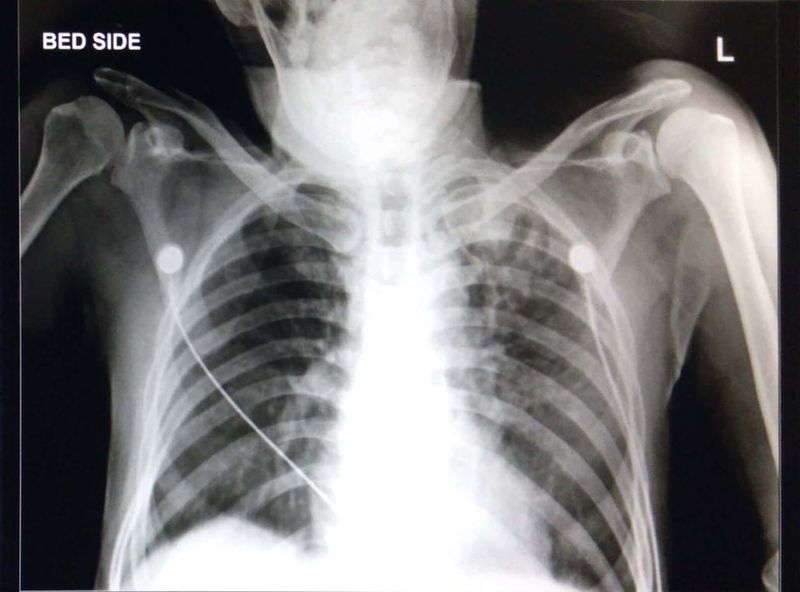

What is the diagnosis?! Patient was thrombolysed with reteplace and 10mins apart patient had blood vomiting.... is it the complication after the thrombolysis or is it tuberculosis or tumour or anything else?!

Old Koch’s sequel.... seen in the left upper lobe of the lung!!!